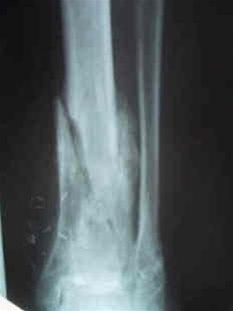

Osteomyelitt nederst i leggbeinet.Osteomyelitt er en bakterieinfeksjon (betennelse) i et ben. Hos barn kommer ofte sykdommen brått på, med sykdomsfølelse, feber, frysninger, smerter og ømhet i den knokkelen som er rammet. Små barn kan ha mer diffuse symptomer og tegn. Nedsatt bruk av en arm eller et bein uten forutgående skade kan skyldes osteomyelitt. Også voksne kan ha et mer snikende sykdomsbilde uten så typiske symptomer.

Mistanke om sykdommen vekkes når den syke angir smerter og ømhet i en knokkel, og det samtidig foreligger en febersykdom. Svar på blodprøver vil kunne styrke mistanken om osteomyelitt. Ofte finnes forhøyet CRP, senkning og antall hvite blodlegemer i blodet, men ikke alltid hos små barn. Vanlig røntgen viser ikke alltid forandringer ved denne tilstanden, det er MR som er den beste undersøkelsen. Noen ganger kan det være aktuelt å ta prøver fra det betente beinet for å finne ut hvilken bakterietype som er skyld i infeksjonen. Det gjøres ved å stikke en nål inn i det betente vevet, ofte under veiledning av ultralyd, CT, MR eller røntgen. Klarer man å identifisere bakterien, kan man finne ut hvilket antibiotikum som hjelper best mot betennelsen.